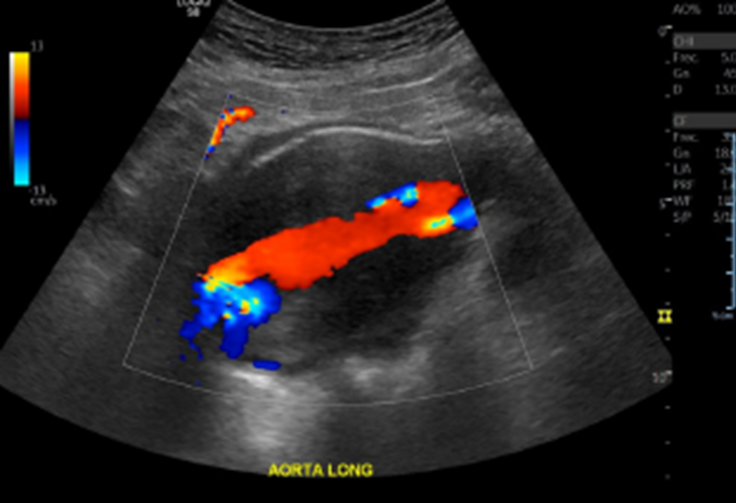

• Por curvas observadas se realiza estudio proximal y se observa gran AAA infrarrenal asociado a trombo mural que ocluye gran % de la luz del vaso.

Hallazgos: Con transductor lineal de alta frecuencia se explora el territorio arterial de la extremidad inferior derecha incluidas las arterias femorales común, femoral superficial, poplítea, tibiales anterior y posterior, peronea y pedia. Placas de ateroma calcificadas en todo territorio arterial de la extremidad inferior, con extensa placa a nivel de la arteria femoral común y profunda generando estenosis de aproximadamente 75% (aumento de velocidad peak sistólico desde 50 cm/s hasta 244 cm/s), con curvas espectrales de morfología parvus tardus en arteria femoral profunda distal a la estenosis. Oclusión completa de la arteria femoral superficial distal, con desarrollo de colaterales que permiten flujo hacia la arteria poplítea. Disminución de velocidad peak sistólico del resto de los vasos de la extremidad inferior, con curvas espectrales de morfología monofásica y parvus tardus. Incidentalmente, se observa aneurisma fusiforme de la aorta abdominal a nivel infrarrenal, en una extensión aproximada de 11.7 cm, con diámetro transverso de 7. 2 cm y anteroposterior de 6.9 cm, con prominente trombo mural que determinan gran disminución del lumen arterial.

Ateromatosis cálcica difusa de la extremidad inferior con extensa placa a nivel de la arteria femoral común y profunda generando estenosis de aproximadamente 75%. Oclusión completa de la arteria femoral superficial distal, con desarrollo de colaterales que permiten flujo hacia la arteria poplítea. Marcada insuficiencia arterial del resto de los vasos de la extremidad inferior. Voluminoso aneurisma fusiforme de la aorta abdominal a nivel infrarrenal, con prominente trombo mural que determinan gran disminución del lumen arterial. Es indispensable evaluación clínica y complementar estudio con AngioTAC de abdomen y pelvis y extremidades inferiores.